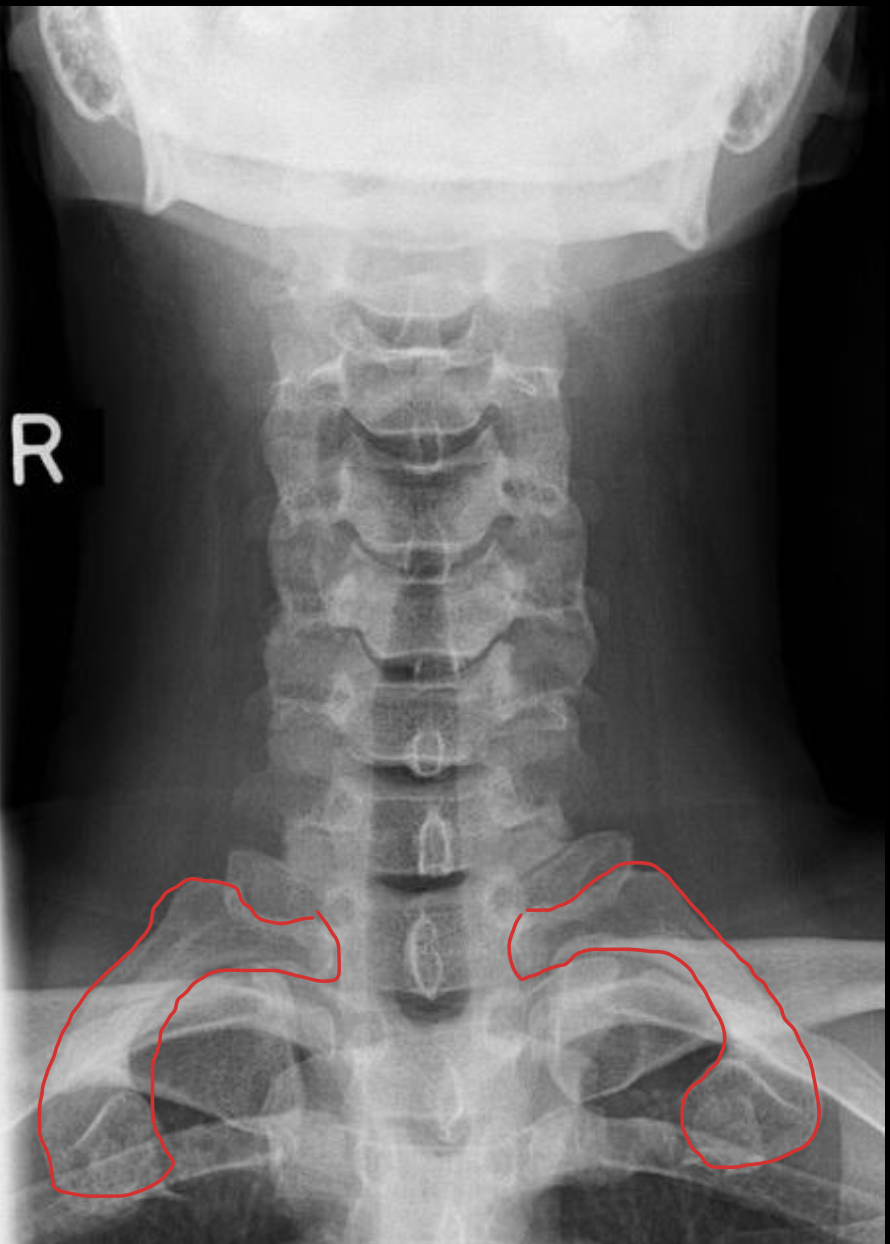

钩突

Uncinate process

关节柱 / 侧块

Articular pillars

棘突

Spinous process

T1

1st rib